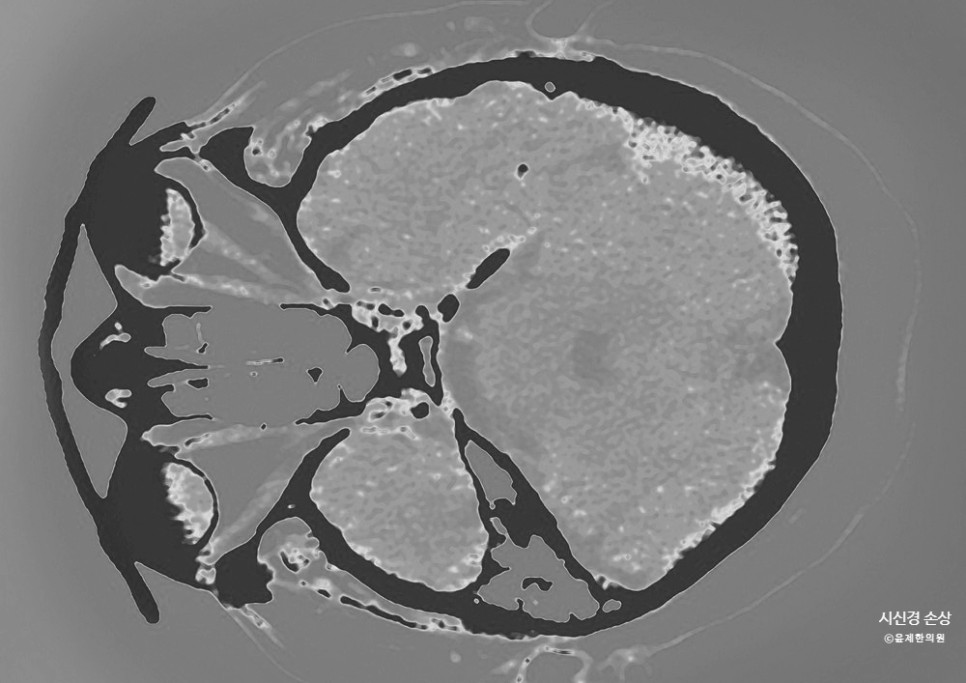

안구 헤드 단면 시티